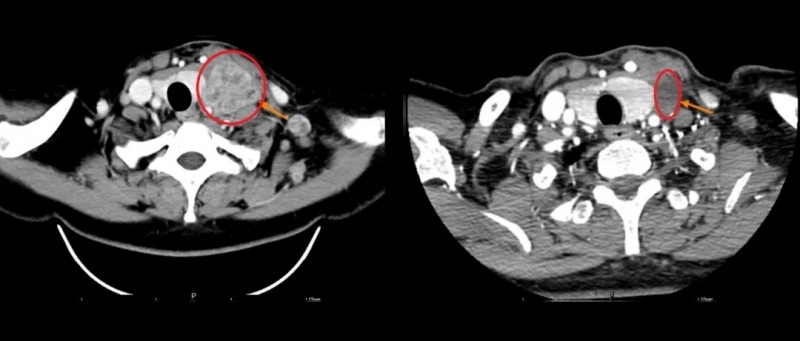

回输后6周,首次疗效评估就让人振奋:整体靶病灶缩小31.9%,其中62mm的最大单病灶缩小近40%,达到部分缓解(PR)。更让人安心的是,他仅出现寒战、发热等轻微不良反应,对症处理后快速恢复,没有出现任何严重不适。

另一例肢端型黑色素瘤患者病情更为严重:右足底病灶增大至近9cm,无法正常行走,且出现肺、胸膜及腹腔等重要内脏转移,经PD-1单药、双免疫联合治疗后仍反复进展。2024年底,她入组GC101 TIL临床试验,2025年初完成回输。回输18周后,左肺、腹腔、右足底病灶分别缩小47.4%、31.7%、36.0%,整体评估为部分缓解(PR),身体状态大幅好转,重新恢复行走能力。